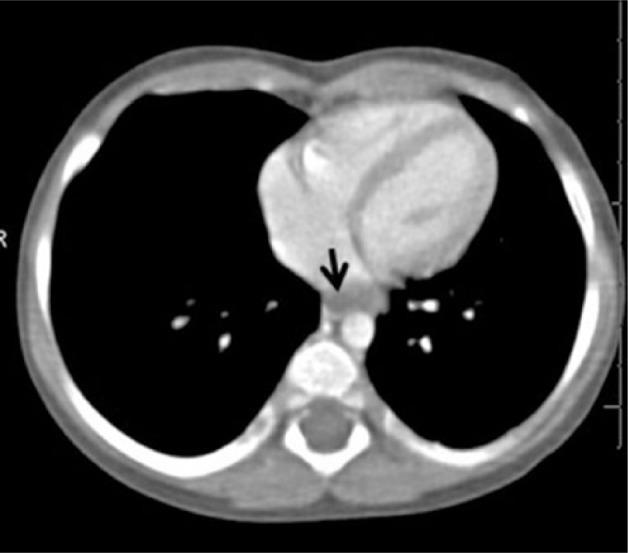

An Unusual Cause of Pediatric Dysphagia: Bronchogenic Cyst.